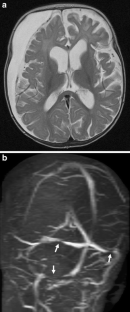

Fig. 1

Fig. 2